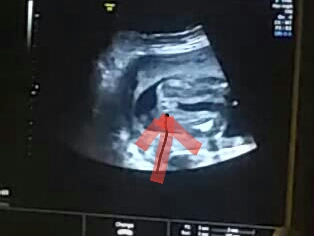

А это с фото картинки узи

На девочку похоже, на 17-ой недели похожая фотография была, половые органы на таком сроке еще немного опухшие у девочки, но четко видно разделение на две половинки должно быть=)) На вашем фото плохо конечно все детали видно. А на счет неуверенности, на 17 недели нам тоже неуверенно сказали..предположили только..и на 21 предположили..на 25 сказали что точно..на 31 подтвердили что точно.

Мне моя сношельница, она узистка, посмотрела видео с моего узи и эти фотки и сказала что это девочка, ни чего не торчит. И та фотка которая типо мне все тут сказали что торчит там и яйца, то это не оно, это копчик. Вообщем все объяснила и показала и уверила что это девочка. Ну и та узистка тоже уверенно сказала что девочка. Это мне тут на сайте наговорили, что мальчик. Ну и надеюсь что не ошибка.